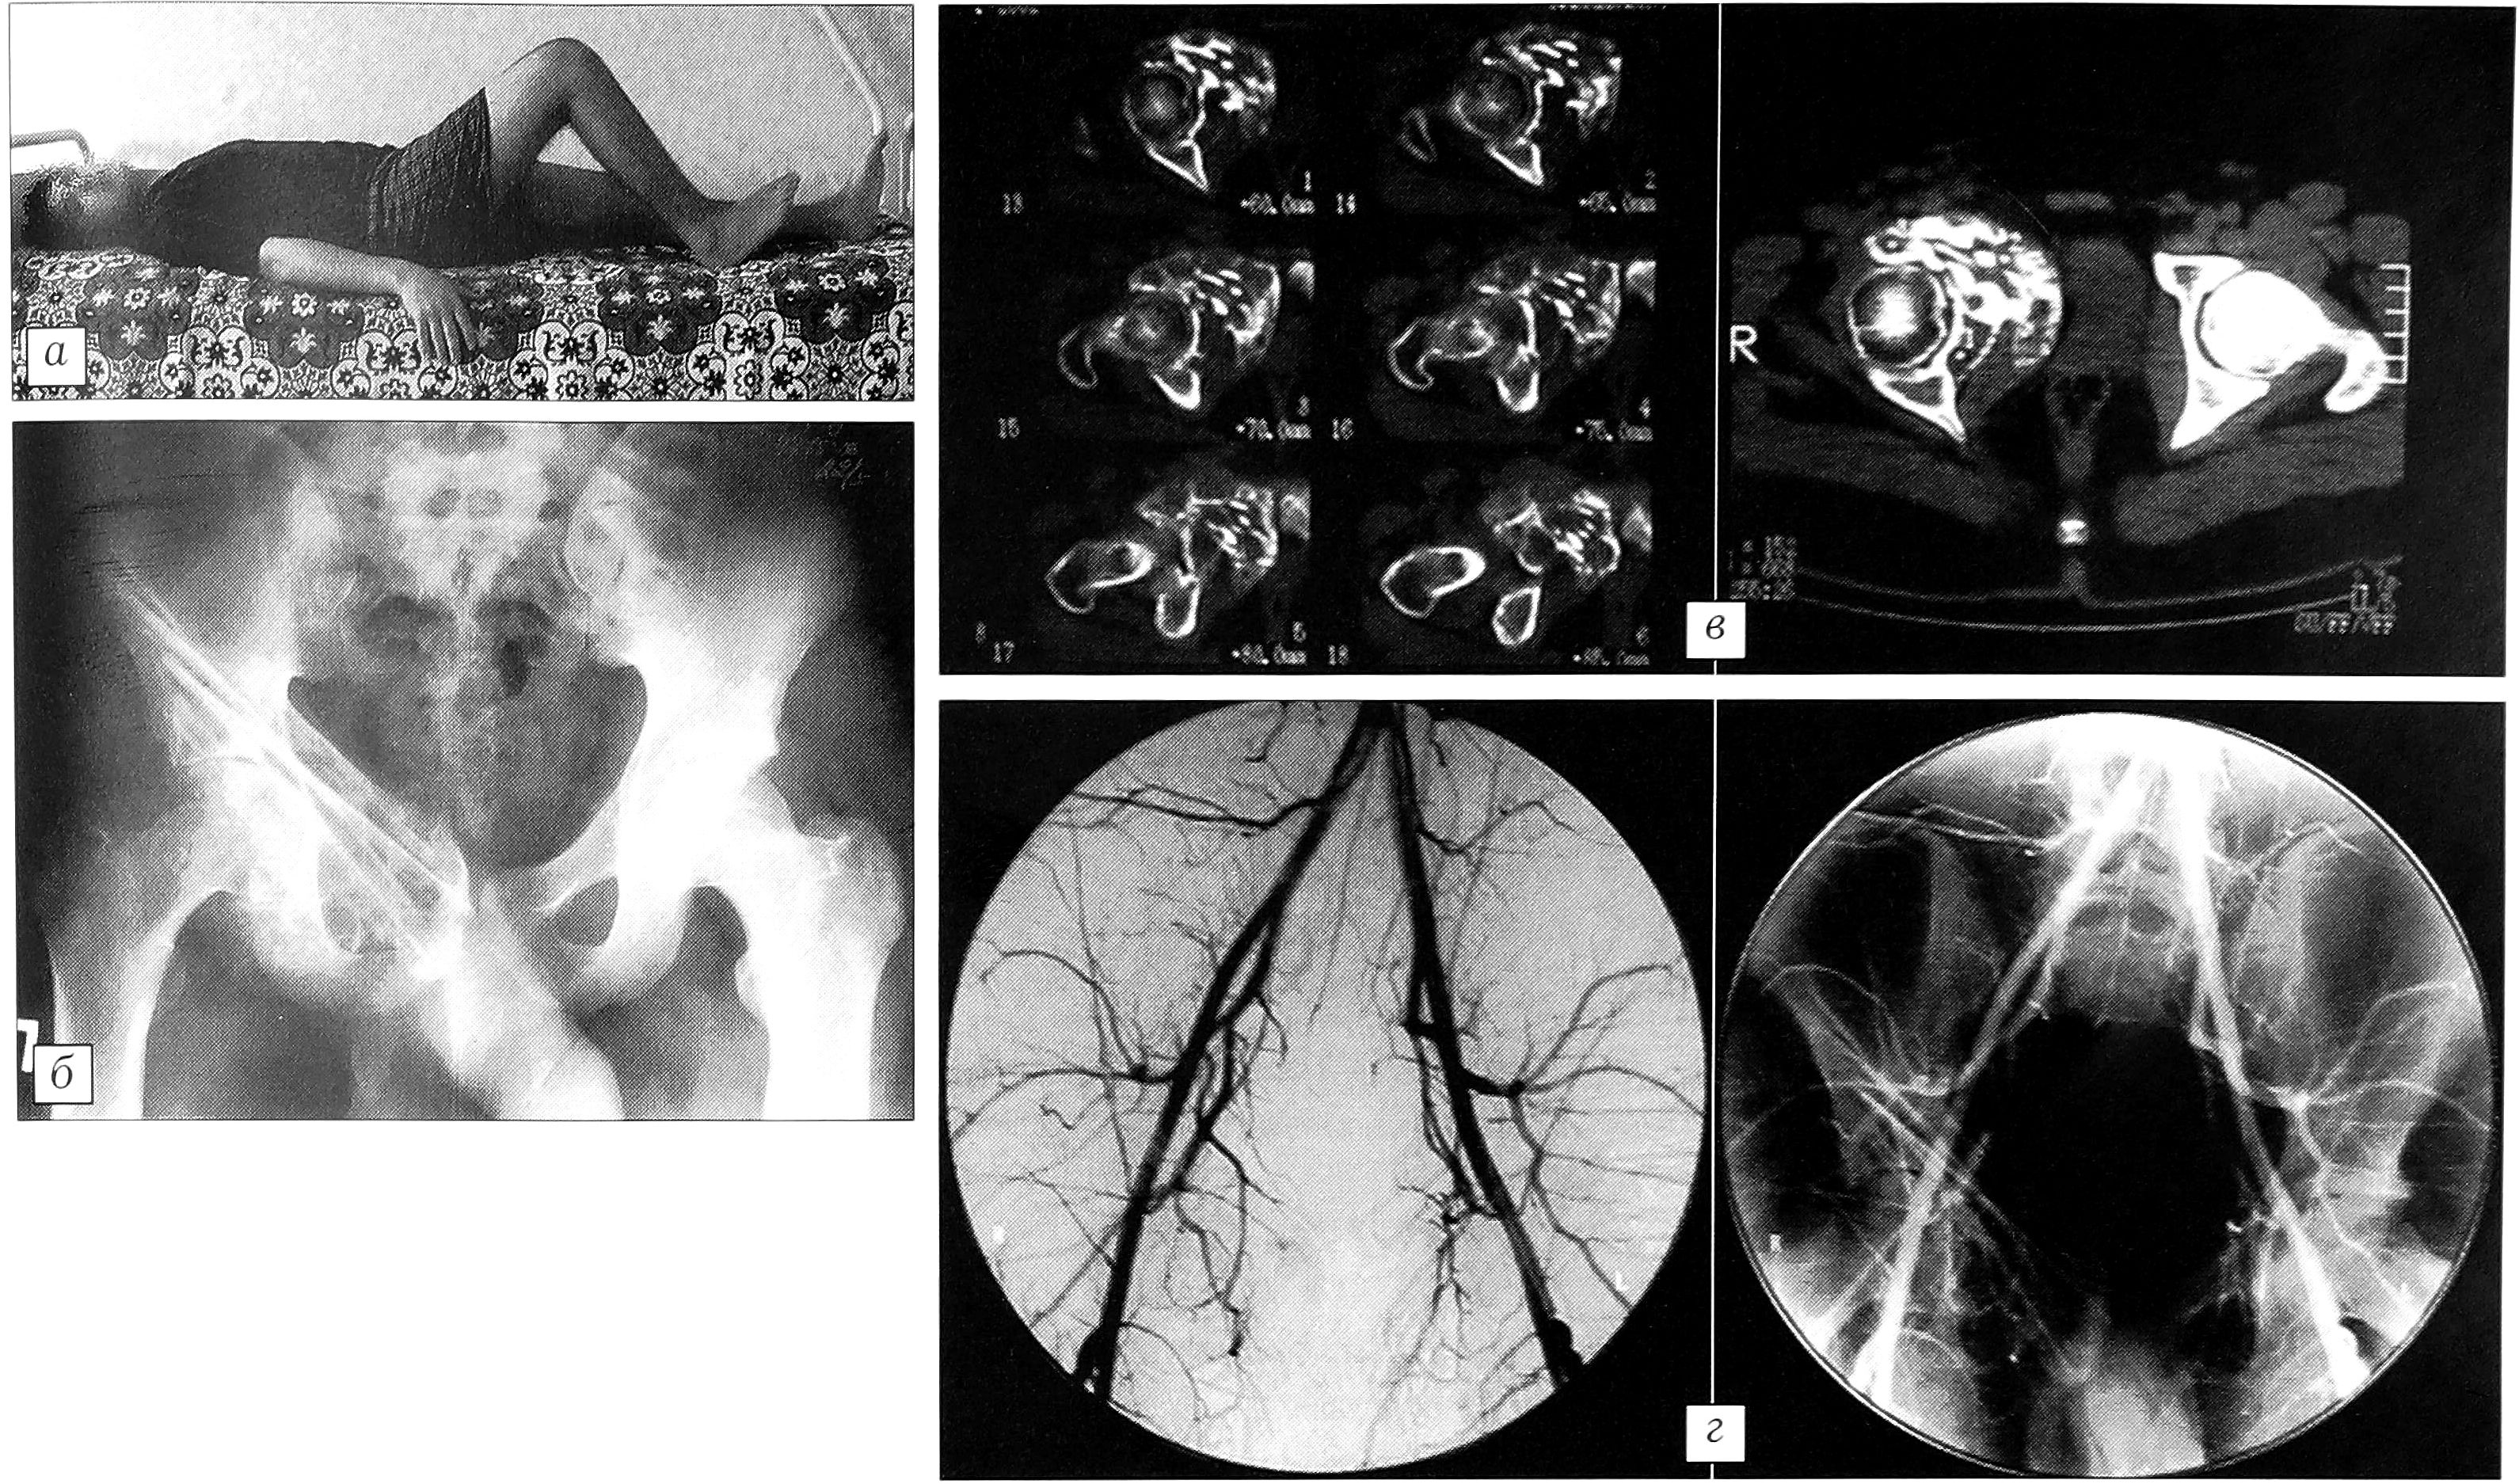

При контрольном обследовании через 6 мес после операции пациент жалоб не предъявляет, движения в правом тазобедренном суставе: разгибание 180°, сгибание 120°, отведение и приведение по 20° (рис 9, а). На рентгенограмме и компьютерной томограмме признаков рецидива нет, отмечается органотипическая перестройка трансплантатов (рис 9, б, в). При контрольной ангиографии патологической сосудистой сети в области операции не выявлено (рис. 9, г).

Рис. 9. Через 6 мес после операции. а — функция правого тазобедренного сустава; б — рентгенограмма таза, в — компьютерная томограмма: рецидива нет, органотипическая перестройка трансплантатов; г — ангиограмма: патологической сосудистой сети нет.